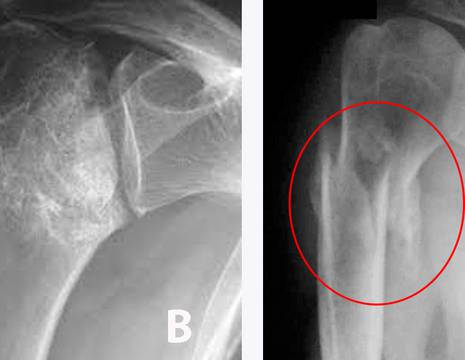

A sublussazione inferiore dovuta ad una paresi del nervo ascellare. B necrosi secondaria post-frattura dell’epifisi omerale. C mancata consolidazione della frattura (pseudoartrosi). D frattura del trochite omerale consolidata in posizione erronea che provoca impingment subacromiale.